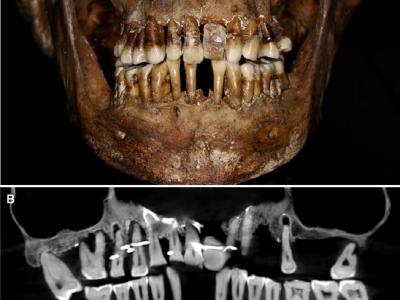

科学家一位法国贵族去世400年后发现她埋

17世纪法国贵族安妮·德阿莱格里(Anne d’Alegre)的牙齿,一根金线穿过几颗牙齿。...